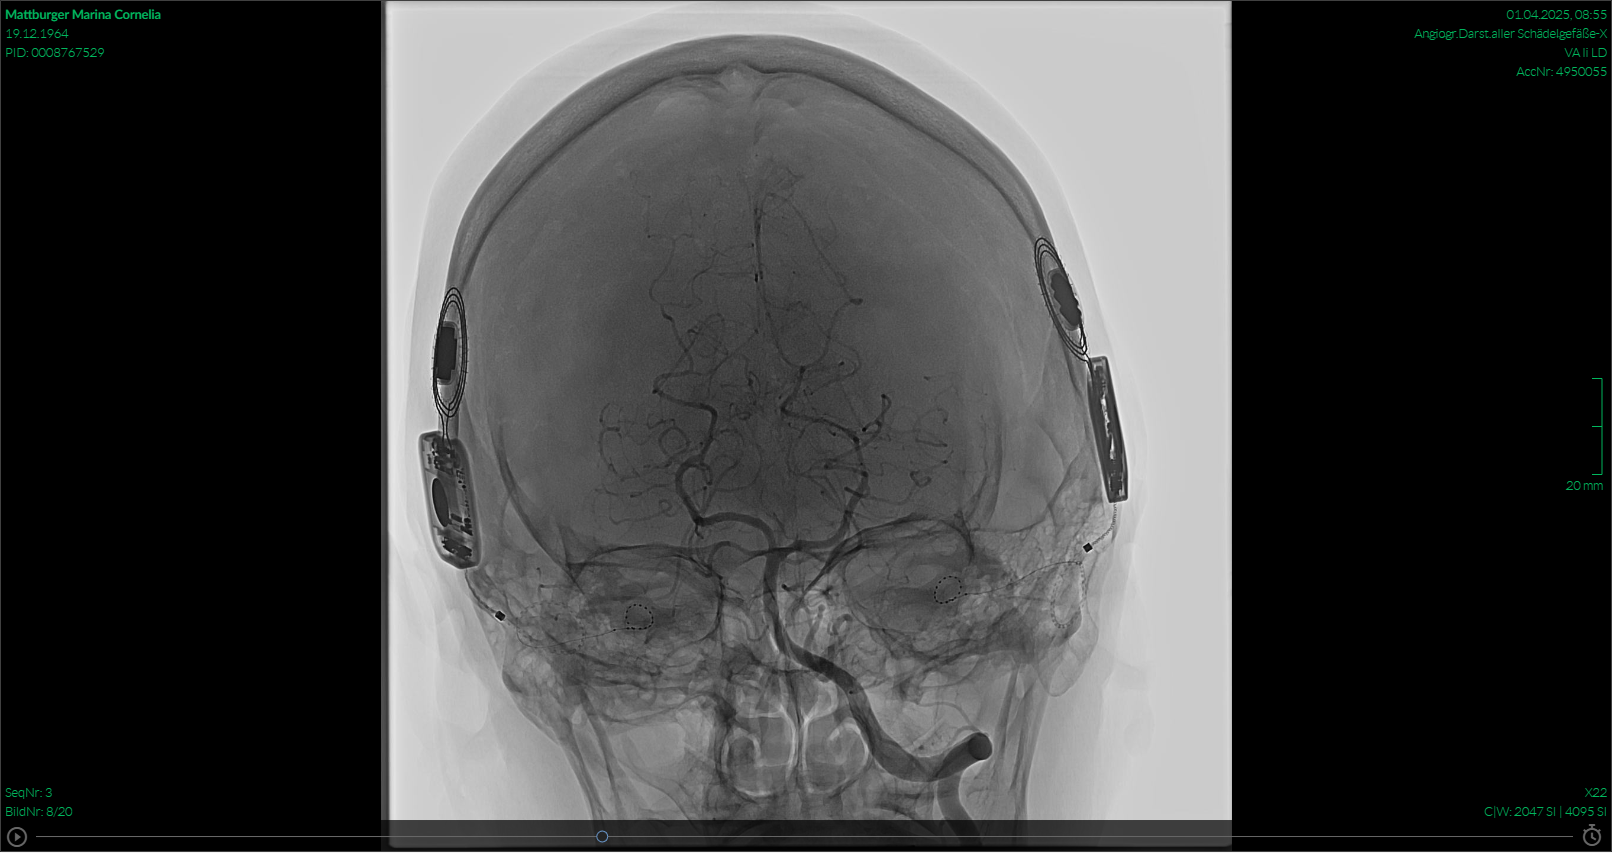

Die Blutabnahme auf der Intensivstation hat auch nicht viel an den Tag gebracht. Daher entschied man sich, eine Untersuchung der Blutgefäße im Kopf zu machen. Eine digitale Subtraktionsangiographie-Untersuchung (kurz DSA genannt) zeigte wahnsinnig tolle Bilder, aber auch bei dieser Untersuchung kam zum Glück nichts raus.

Es ist eine Untersuchung, die mit einem Katheter in der Armvene und ständiger Gabe von Kontrastmittel stattfindet. Für den behandelnden Arzt war es auch was ganz Neues, jemanden Gehörloses hatte er noch nie auf der Liege. Aber da er mir, so lange ich das CI noch tragen konnte, alles bestens erklärt hat, wusste ich Bescheid und habe mich keinen Millimeter bewegt, die ganze Sache auf dem großen Bildschirm etwas beobachten können und im richtigen Moment genau das getan, was er mir gesagt hatte.

Luft anhalten und erst wenn das Kontrastmittel dort ankommt, wo es sein soll (das merkt man sehr deutlich) wieder weiteratmen. Also, ich habe wohl alles richtig gemacht.

Es geht mir wieder gut, das ist die Hauptsache. Die Bilder zeigen Aufnahmen vom MRT und von der Subtraktionsangiographie. Ich hoffe, ich mache euch ein wenig Mut, keine Angst vor solchen Untersuchungen zu haben. Auch mit CI geht das!